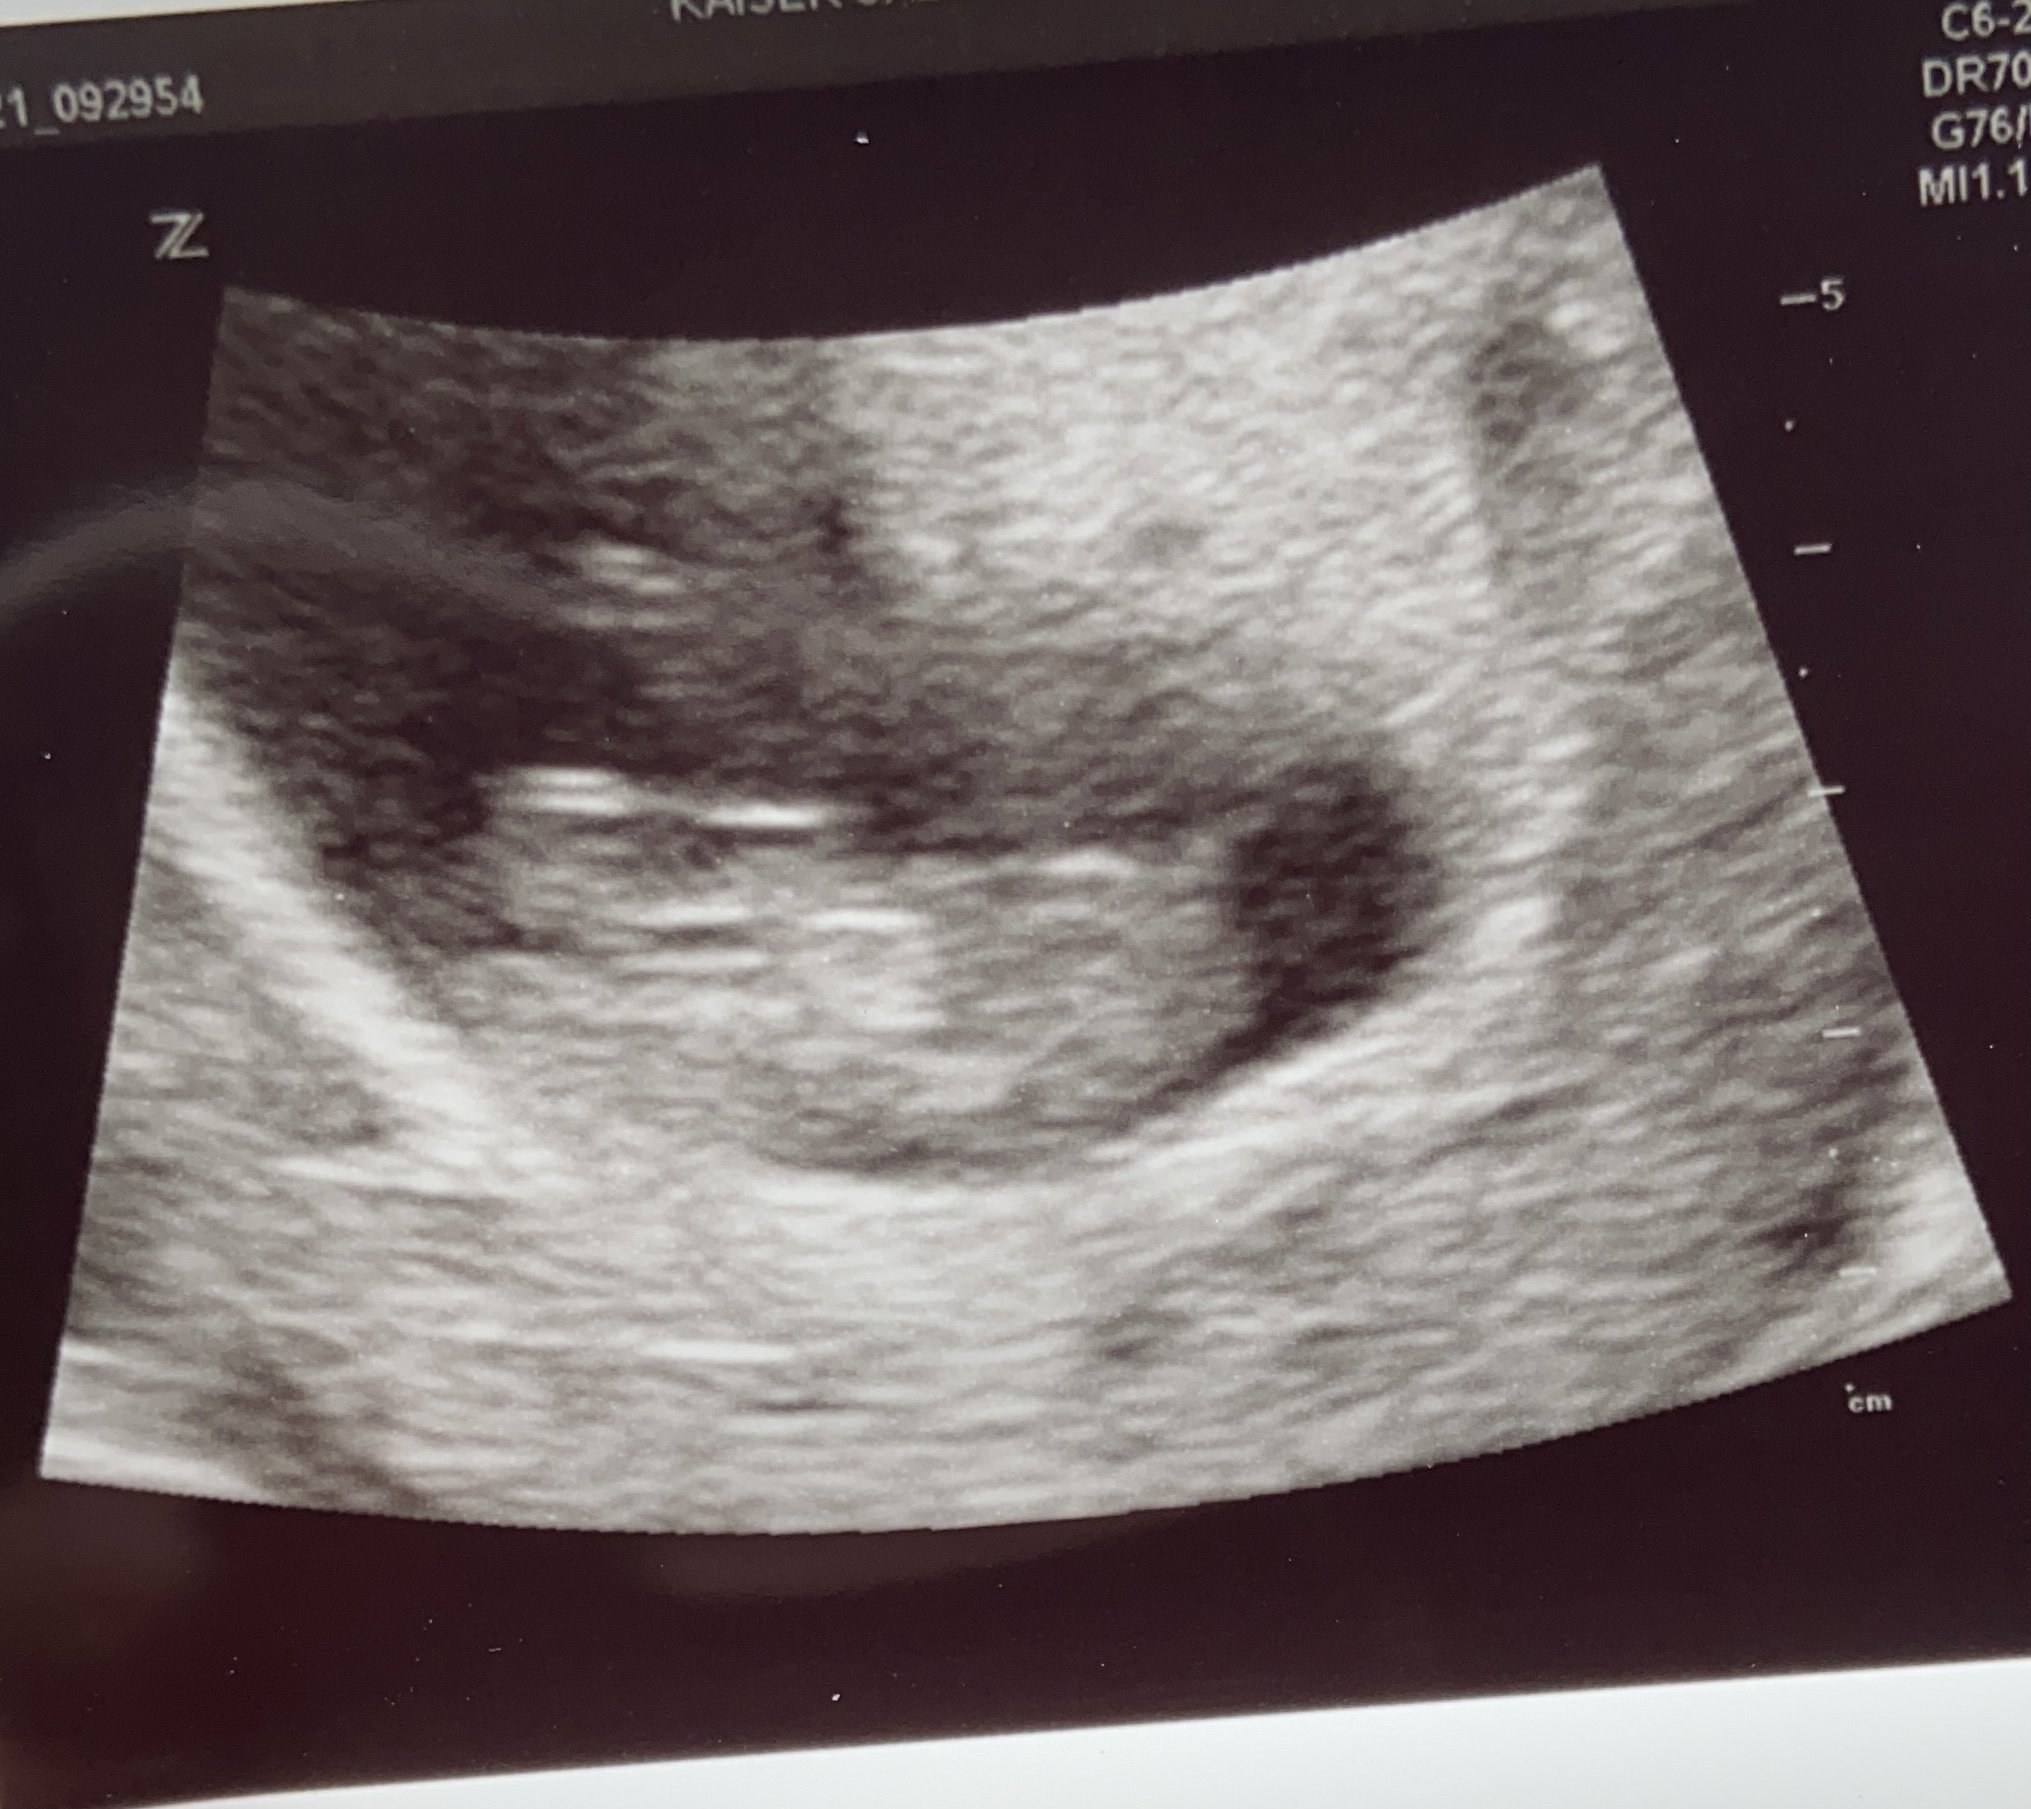

This was my second ultrasound! Baby was measuring ahead. I was 9 weeks 5 days at the time of the ultrasound, measuring 10 weeks 3 days. I’m 11 weeks 4 days now and looking forward to my next ultrasound in a week